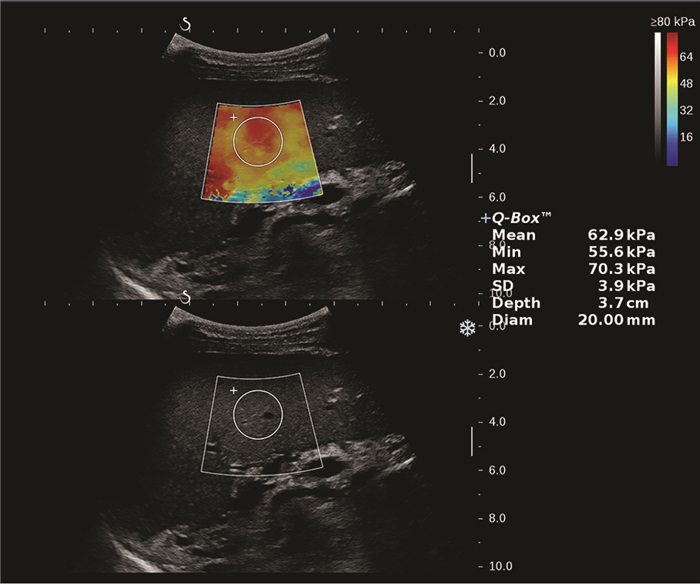

Clinical value of two-dimensional shear wave elastography in predicting esophageal varices in patients with hepatitis B cirrhosis by evaluating liver and spleen stiffness

Xuemei WANG, Yao ZHANG, Xueping YANG, Yue WANG, Mixue WANG

2021, 37(5): 1081-1084. DOI: 10.3969/j.issn.1001-5256.2021.05.021

Abstract(1360) HTML (289) PDF (2305KB)(71)

Abstract:

Objective  To investigate the value of two-dimensional shear wave elastography (2D-SWE) in the noninvasive evaluation of the presence or absence of esophageal varices (EV) in patients with hepatitis B cirrhosis by liver stiffness measurement (LSM) and spleen stiffness measurement (SSM).  Methods  A total of 172 patients who were diagnosed with hepatitis B cirrhosis in Beijing Ditan Hospital, Capital Medical University, from April 2019 to February 2020 were enrolled in a prospective study, and according to the results of gastroscopy, they were divided into non-EV group and EV group. The two groups were compared in terms of spleen thickness (ST), spleen diameter (SD), LSM, and SSM. The independent samples t-test was used for comparison of normally distributed continuous data between two groups, and the Mann-Whitney U test was used for comparison of non-normally distributed continuous data between two groups; the chi-square test was used for comparison of categorical data. The receiver operating characteristic (ROC) curve was used to investigate the value of LSM and SSM in the diagnosis of EV, and the Z test was used to compare the diagnostic accuracy of LSM and SSM.  Results  There were 121 patients in the EV group and 51 patients in the non-EV group. There were significant differences between the two groups in ST (t=8.143, P < 0.001), SD (t=7.363, P < 0.001), LSM (Z=3.024, P=0.002), SSM (t=15.142, P < 0.001), and presence or absence of ascites (χ2=22.101, P < 0.001). LSM had an area under the ROC curve (AUC) of 0.646 (95% confidence interval [CI]: 0.570-0.718) in the diagnosis of EV, with a sensitivity (Se) of 83.47%, a specificity (Sp) of 47.06%, a positive predictive value (PPV) of 78.9%, and a negative predictive value (NPV) of 54.5% at the optimal cut-off value of 13.16. SSM had an AUC of 0.951 (95% CI: 0.907-0.978) in the diagnosis of EV, with an Se of 80.99%, an Sp of 96.08%, a PPV of 98.0%, and an NPV of 68.1% at the optimal cut-off value of 38.08. SSM had a better diagnostic accuracy than LSM (Z=6.096, P < 0.001).  Conclusion  LSM and SSM can be used to predict the presence or absence of EV in patients with hepatitis B cirrhosis. SSM has a higher accuracy than LSM and can provide accurate diagnostic information for clinical practice.